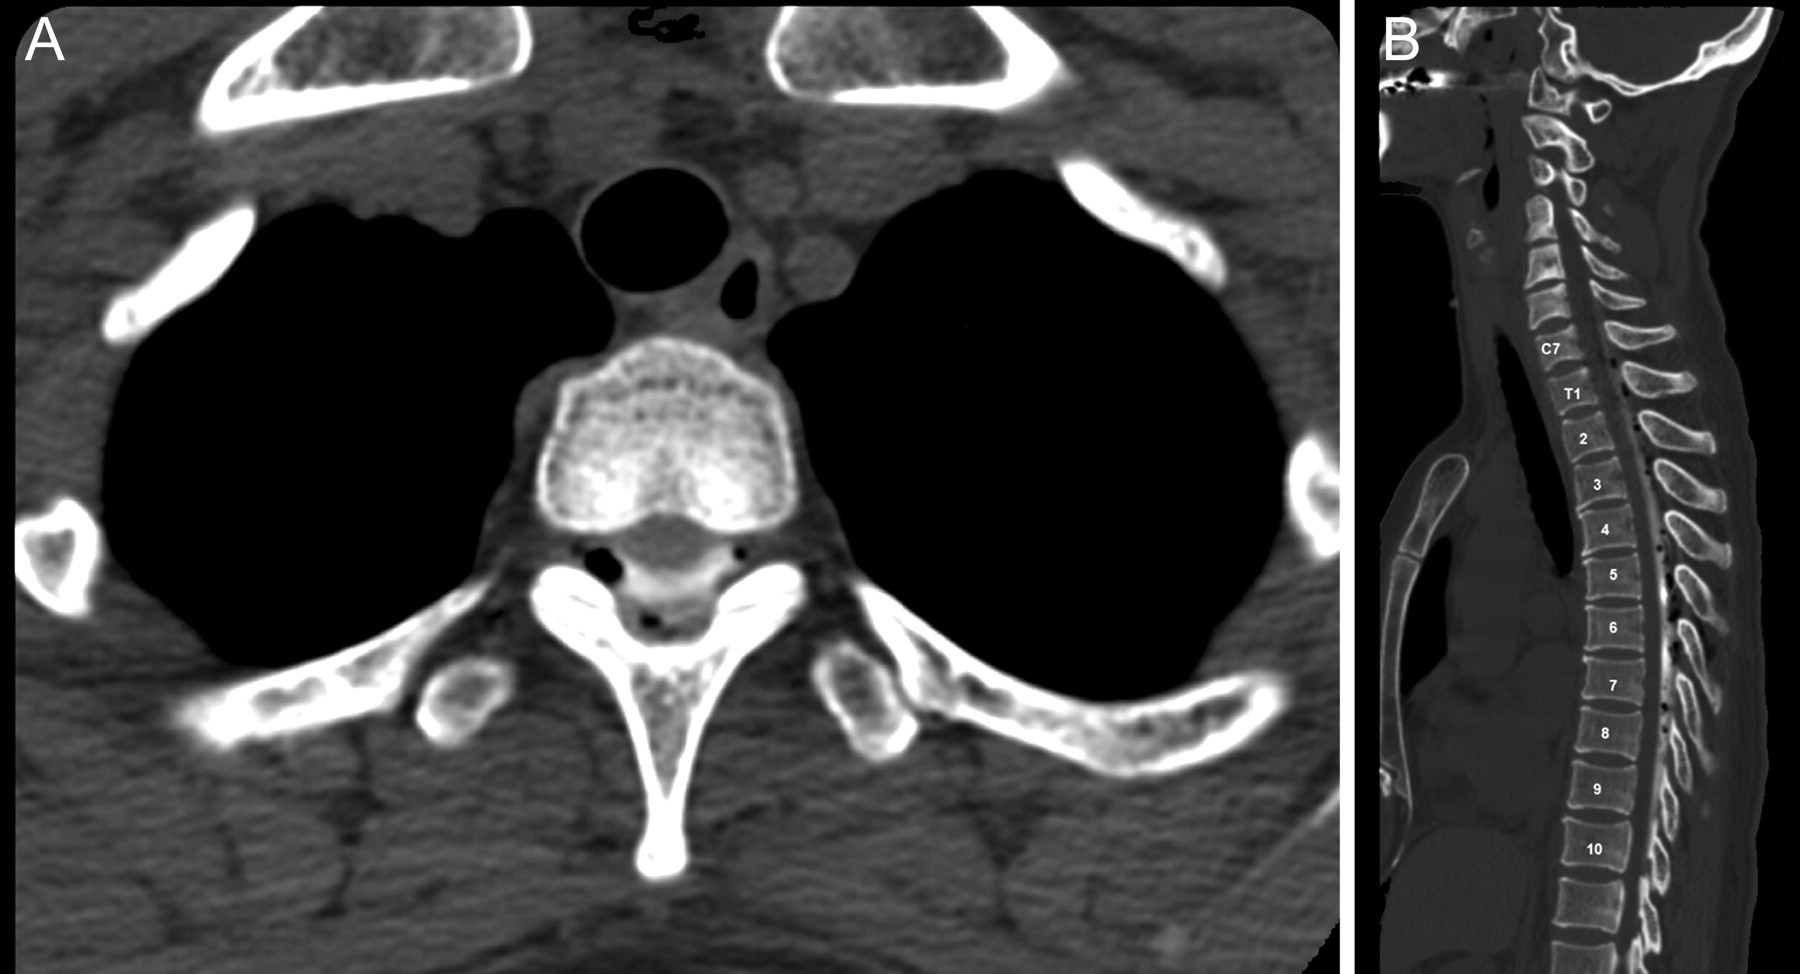

针对EBP也放置使用21-gauge爵针使用相似的技术用于EBP视而不见。硬膜外腔后,在目标位置被确定阻力损失的技术,准确的定位终于透视下经硬膜外腔造影术。此后,荧光镜的指导下在俯卧姿势,10 - 15毫升的自体血混合着对比剂(1 - 2毫升iopamidol)注射,使血液补丁的传播观察(图2)。病人至少保持仰卧的EBP放置后24 - 48小时之内。所有患者接受脊椎CT EBP位置确认后立即修补的分布有针对性的硬膜外腔周围的血液(图3)。没有响应EBP或复发病例在EBP,我们考虑重复EBP。随访时间从6个月到5年不等的意思是4.2年。

技术细节可以提高成功。荧光镜的指导是理想确认针的位置提示硬膜外腔内和硬膜外腔造影术可以确认硬膜外修补区域涵盖了脑脊液漏的位置。此外,9至10毫升的血液的混合物和1毫升的对比剂将直接指导修补血液进入硬膜外腔的分布。最后,脊髓CT扫描后立即获得EBP可以显示分布的修补硬脑膜的囊周围的血液沿着脊柱的长度和是否修补血液适当覆盖硬膜外腔。液体注入血液的一致性在硬膜外的管理也应该被考虑。注入的血液不能沿长轴分布的脊柱由于其粘度。在目前的研究中,脊髓CT扫描后立即执行EBP表明注射自体血与对比剂混合涉及脊柱的各个水平的数量(从5到6到10 - 12水平)从主网站注入。尽管如此,我们建议注射部位应尽可能附近主要的脑脊液漏。